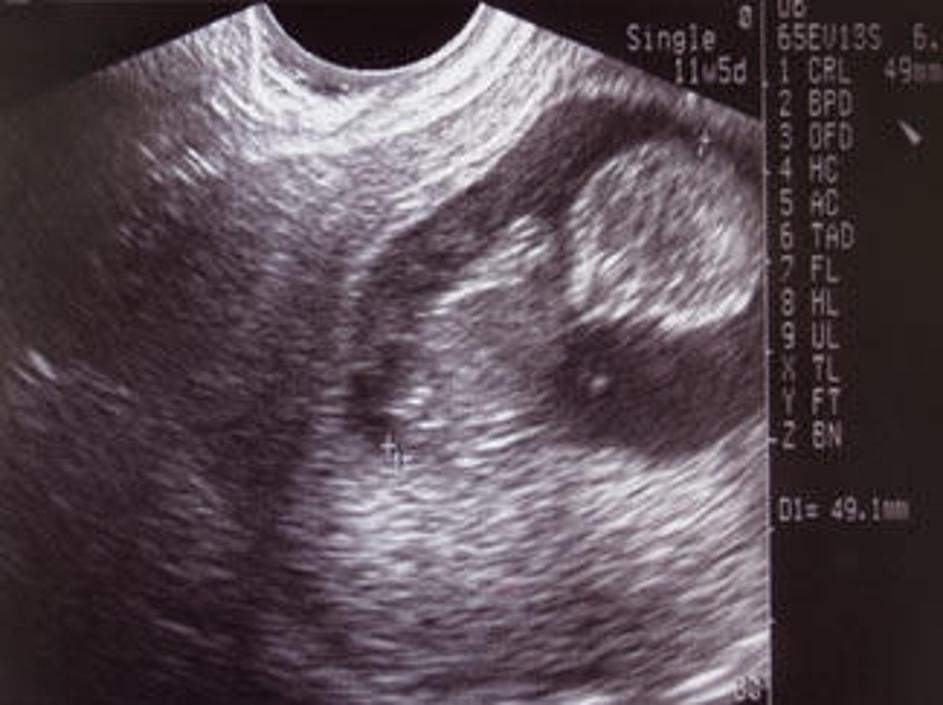

Na kliniki naj bi splav opravilo več tisoč žensk. Žurnal24 Na kliniki naj bi splav opravilo več tisoč žensk.